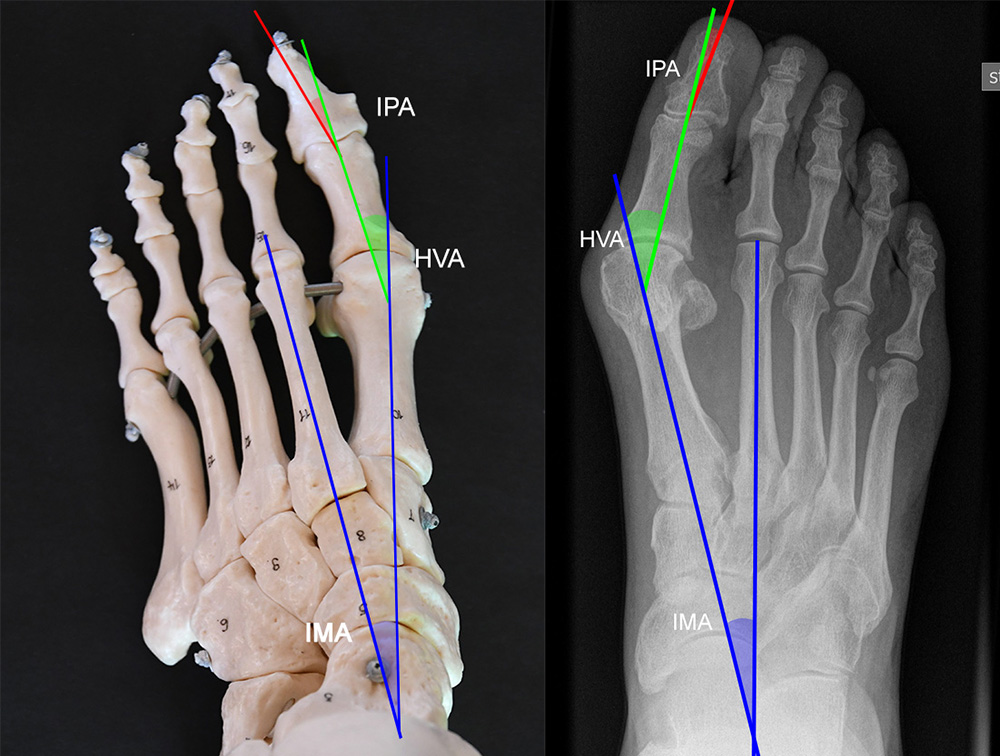

Vermessung der belasteten Aufnahmen des Fußes

Winkelmessungen am Fußskelett beziehen sich sämtlich auf belastete Aufnahmen 6. Die folgenden Aufnahmen zeigen die üblicherweise verwendeten Winkelmaße und ihre Definition. Viele Fehlstellungen des Fußes betreffen den Vor- und Rückfuß. Dies sollte bei der Beurteilung der Bilder und der Therapieplanung stets berücksichtigt werden.

Beurteilung von Fehlstellungen des Vorfußes

Zur Vollansicht und zum Lesen der Bildbeschreibung bitte die Bilder anklicken.

Gelenkflächenwinkel

DMAA (Distal metatarsal artikular angle, Syn. Gelenkflächenwinkel): Winkel zwischen der Achse des Os metatarsale I (rot) und dem Lot auf die distale Gelenkflächenebene (blau) des Os metatarsale I. Die Gelenkflächenebene (grün) wird definiert durch zwei Punkte, welche die mediale und laterale Begrenzung der Gelenkfläche definieren (Norm: <10° 5). Die Projektion des DMAA ist stark abhängig von der Rotation des Os metatarsale I 7. Daher ist bei der operativen Behandlung des Hallux valgus eine Beurteilung häufig erst nach Korrektur der Pronationsstellung des Os metatarsale I möglich. Tendenziell wird der DMAA auf präoperativen Röntgenaufnahmen überschätzt.

Beurteilung eines Metatarsus adductus

Medial wird eine Linie von der medialen Begrenzung des TMT1-Gelenks und der medialen Begrenzung des Talonavikulargelenks (TN) gezeichnet. Auf der lateralen Seite des Fußes wird eine zweite Linie von der lateralen Begrenzung des Calcaneocuboid-Gelenks (CC) zur lateralen Begrenzung des TMT5-Gelenks gezeichnet. Die Mittelpunkte beiden Linien werden verbunden (blau). Der Winkel zwischen der Achse des Os metatarsale II (rot) und dem Lot auf Verbindungslinie (grün) ist ein Maß für die Stellung des Vorfußes zur Fußwurzel. Dieser Wert dient zur Charakterisierung eines Pes adductus. Ein Pes adductus kann zu einem normwertigem Intermetatarsale I/II Winkel führen, obwohl klinisch eine ausgeprägte Hallux valgus Deformität vorliegt 8. (Norm: ±13° 9.